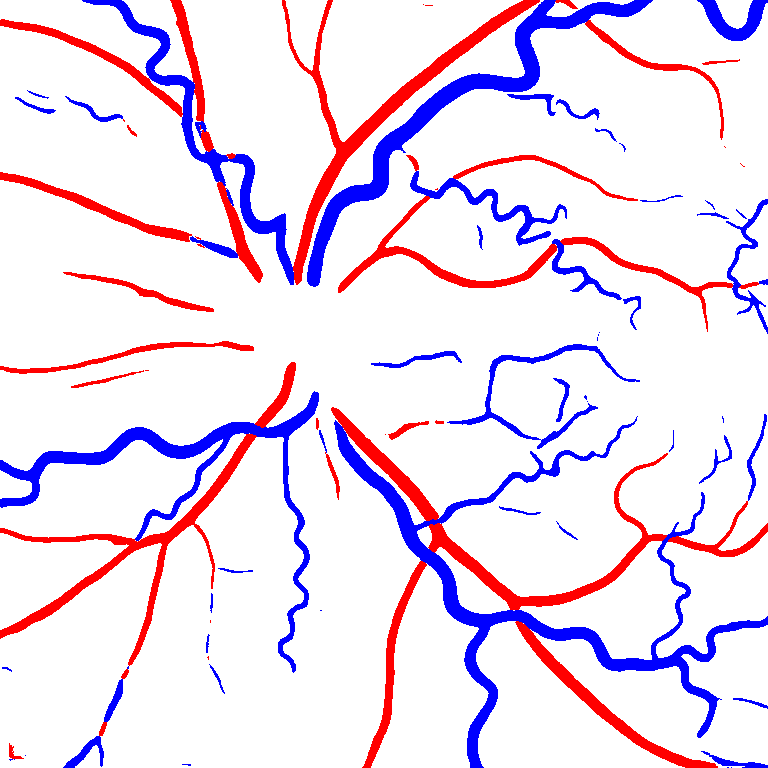

(a) Reference (b) Output (c) Width Map

As reported in Table IV, we compared the SegRAVIR model against competing deep learning-based segmentation approaches on the RAVIR dataset. Evidently, SegRAVIR outperforms these methods as judged by all metrics for artery and vein classes with a healthy margin. In terms of Dice score, SegRAVIR outperforms CE-NET, IterNet and AG-Net by , and for artery segmentation and by , and for vein segmentation, respectively. Fig. 4 presents a qualitative comparison of the semantic segmentation outputs of SegRAVIR, CE-Net, and U-Net. Specifically, SegRAVIR yields more accurate vessel topology (i.e., thickness and orientation) segmentation with higher pixel-wise classification accuracy.

Table VI presents a quantitative comparison of the measured diameters using the segmentation outputs of SegRAVIR and competing approaches. Using the pixel-wise annotated masks, the reference average diameter of the arteries and veins in the test set of the RAVIR dataset were measured as and , respectively. According to our analysis, SegRAVIR can accurately measure the diameter of the vessels and it achieves the smallest MAPE among the competing approaches. Specifically, in comparison to CE-Net, Iter-Net, and DU-Net, respectively, SegRAVIR is on average , and more accurate in terms of MAPE for the measured diameter of arteries and , and in terms of MAPE for the measured diameter of veins. Fig. 6 presents qualitative comparisons of reference and SegRAVIR estimated diameter maps.

(a) (b) (c)

(a) (b) (c)